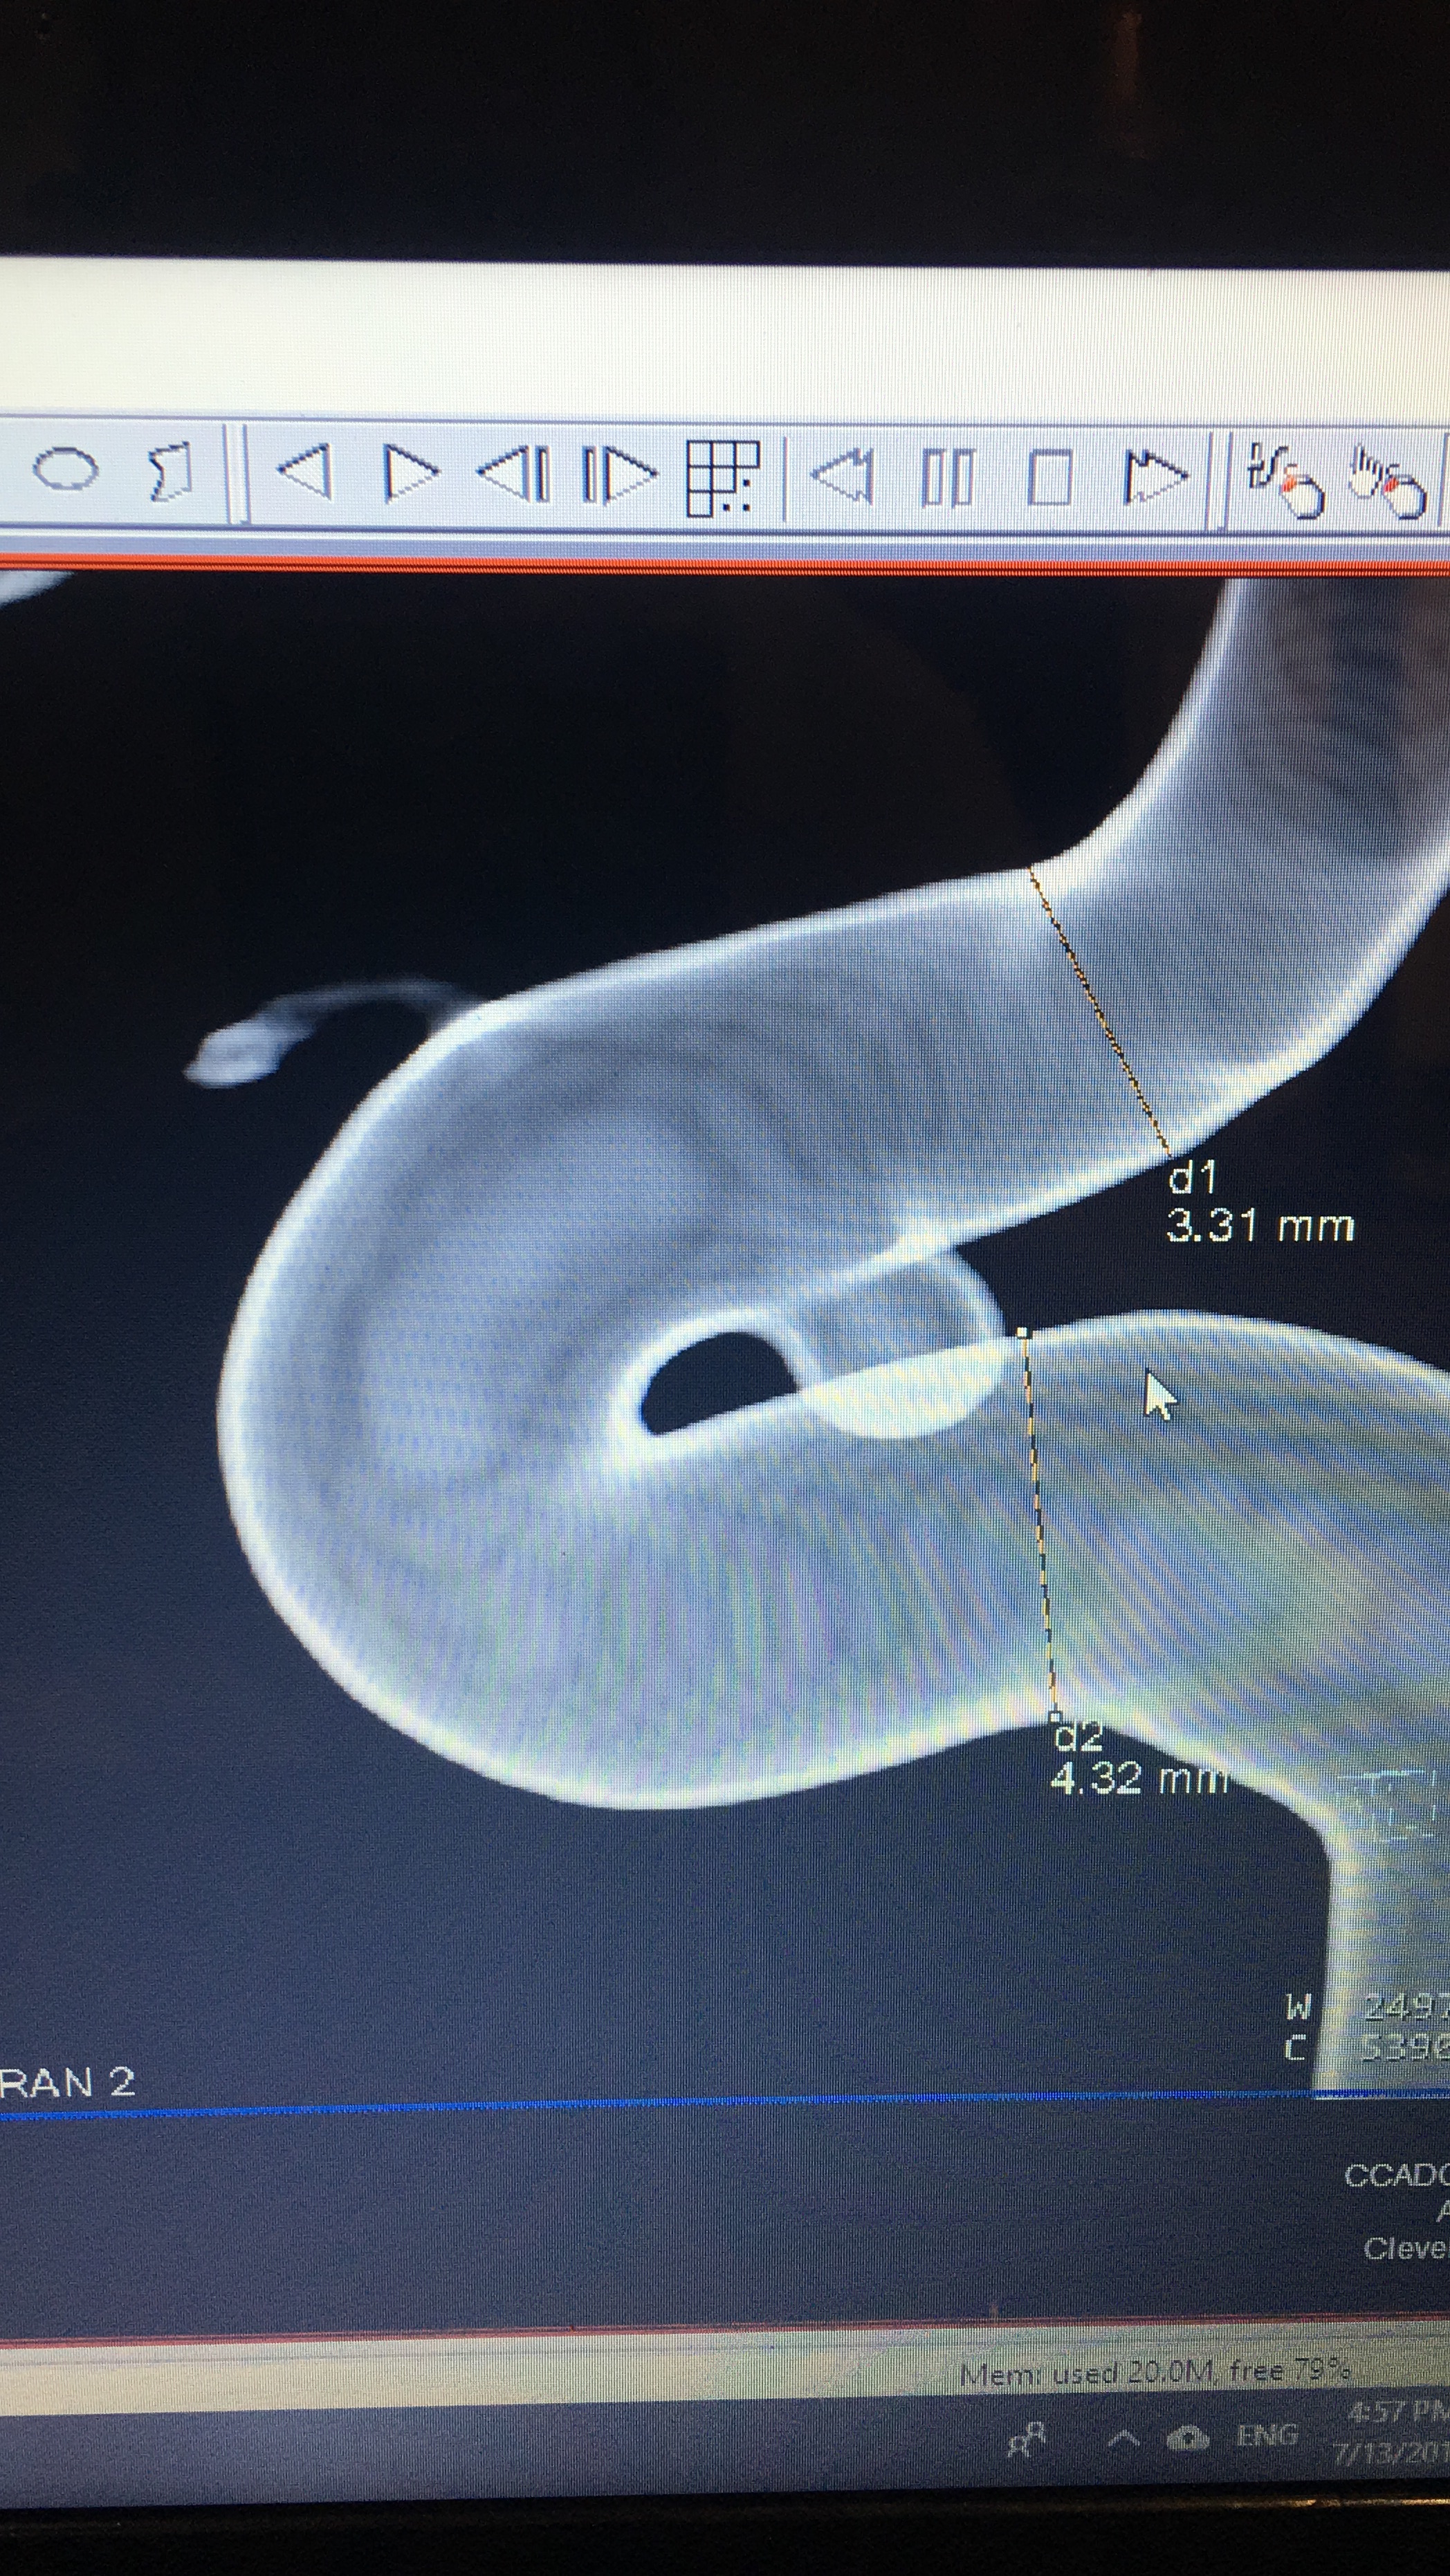

Today, we set date for Endovascular Treatment (Flow Diverter) for July 17th. My annie is 4 x 6.2 and due to the odd/rare shape and how it connect to the opthalmic artery that lead to my left eye, this is the best option FOR NOW! Clipping is not on the table right now as I am on Plavix and Aspirin and they don’t believe Cardiology will agree to stopping either one. I understand this as if they clip the annie, I may end up having a heart attack and Cardiology will likely say “hell no”. Next month will be a year since my heart stent, so there is a possibility I may have been coming off next month but there is no guarantee. On the other hand, since aspirin and Plavix is required for the flow diverter with a requirement for up to at least 6 months, there is a possibility the overlap can give Neurosurgery leverage to level off the aspirin and plavix (only for a couple of weeks for prep and until surgery is over) by that time and do the clipping IF the aneurysm is still active.

As I discussed with my Neurosurgeon, my goal is to control/manage this annie ASAP using the best treatment with the best outcome. He said with my annie there is a 0.5% chance of rupture over the next year. My annie as stated above is oddly shaped which is complicated in terms of risking vision loss. The annie itself is like a bubble but the neck is like a double bubble. It look like a hand is clasped over the annie and it is directly connected to the opthalmic artery. I told my husband that is God’s hand holding my annie! Coiling is off the table as if they filled it with coils, they could possibly fall out and if it clot that clot could easily travel in either direction and cause a stroke. I am comfortable with what we have planned as this is the best option for right now until we can do a clipping, if needed. He indicated there was a good chance the annie could shrink. He said, the primary goal of the flow diverter is to take the pressure off the annie which will ultimately reduce the chance of rupture. I am in good hands with some of the best doctors in the country and I trust their recommendation. Hubby took notes so if I forgot something I will post later once he type them out for me as I cannot read his “doctor” style writing. LOL